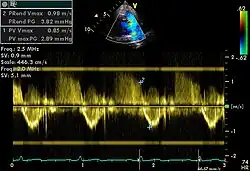

Spectral doppler

Spectral doppler is presented similarly to M-mode in which the doppler information is plotted as a spectrogram. This can be both "continuous" and "pulse" wave where the former shows the spectrum along a specific line and the latter shows within a small window along that line. Continuous wave is better at showing maximal velocities and pulse wave is better for showing flow through a small volume.

Spectral doppler is often used for quantification of flow. For example, the aortic valve area can be estimated using the continuity equation by measuring the velocity time integral (VTI) of the aortic valve & LV outflow tract; the VTI is calculated by tracing the flow on the spectral doppler curve. Spectral doppler is also useful for calculating the maximum flow and mean flow through a valve (used to grade valve stenosis).